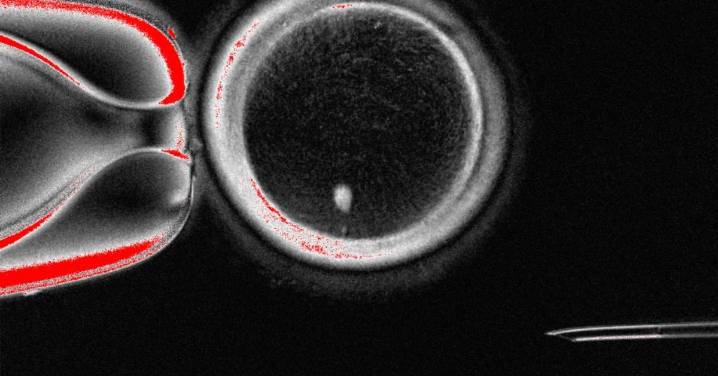

Las células de la piel humana pueden utilizarse para producir óvulos potencialmente fecundables, así lo indica un estudio que publica “Nature” y que ha probado una novedosa técnica, aunque aún es necesaria más investigación para garantizar la seguridad y la eficacia antes de futuras aplicaciones clínicas.

La investigación, liderada por Shoukhrat Mitalipov , de la Universidad de Salud y Ciencias de Oregón (EUA), se trata de una prueba de concepto sobre la posible viabilidad de la programación celular en humanos para tratar la infertilidad .

La infertilidad, que afecta a millones de personas, puede estar causada por la disfunción o la ausencia de una de las dos células sexuales (gametos) – el ovocito (óvulo) o el espermatozoide – necesarias para producir un cigoto (óvulo